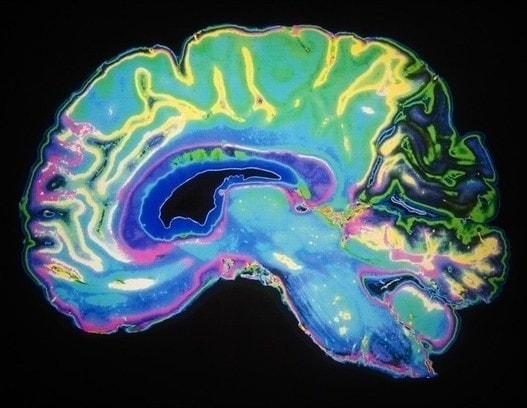

Glioblastoma (GBM) is the most common and aggressive type of cancerous brain tumor in adults. People with GBM generally expect to live 12 to 18 months after diagnosis. Despite decades of research, there is no known cure for GBM, and treatments have only a limited effect on extending an individual’s life expectancy. However, researchers have tested a technology that delivers CAR-T cells targeting two proteins commonly found in brain tumors: epidermal growth factor receptor (EGFR), estimated to be present in 60% of all GBMs, and interleukin-13 receptor alpha 2 (IL13Rα2), which is expressed in over 75% of GBMs. While CAR-T cell therapy for blood cancers is usually administered intravenously, the researchers administered these dual-targeted CAR-T cells intrathecally, by injection into the cerebrospinal fluid, so that the modified cells could reach the tumors more directly in the brain. Magnetic Resonance Imaging scans taken 24 to 48 hours after administration of dual-targeted CAR-T cells targeting EGFR and IL13Rα2 revealed a reduction in tumor size in all six patients, and these reductions were maintained up to several months later in a subgroup of patients.